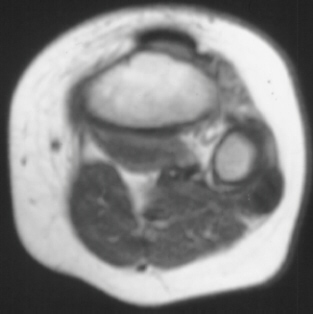

XRAY EVALUATION:

Radiographic examination of the left knee revealed no osseous abnormalities . A fullness of the soft tissues was evident over the fibular head. MRI examination of the left knee displayed a 2 cm. by 0.8 cm. lobulated mass in the region of the common peroneal nerve with no enhancement . On the T-2 weighted sequences there was abnormal increased signal of the tibialis anterior, extensor digitorum longus and peroneus longus muscle bellies suggesting atrophy . EMG/NCS were performed which clearly documented electrodiagnostic evidence of a severe peroneal neuropathy distal to the take-off of the nerve to the short head of the biceps.